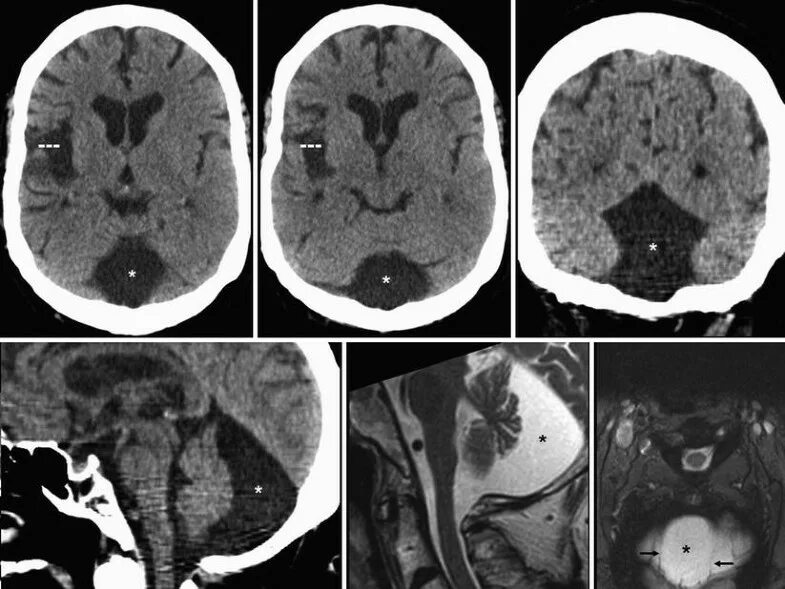

Ретроцеребеллярная ликворная киста